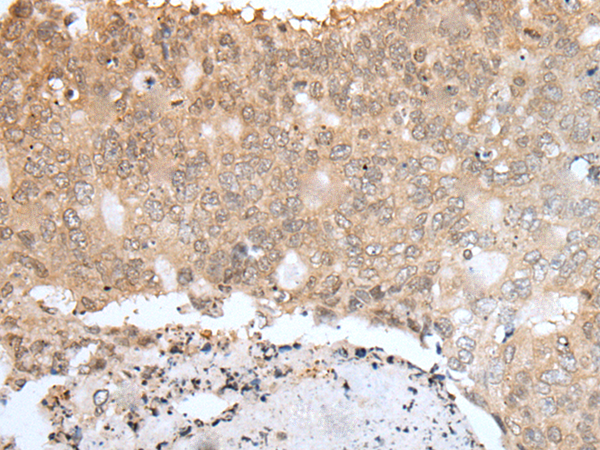

IHC positive control: |

Human esophagus cancer and human colorectal cancer |

IHC Recommend dilution: |

25-100 |